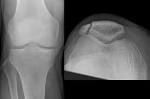

Patella fraktur

Patellar (Kneecap) Fractures-OrthoInfo - AAOS